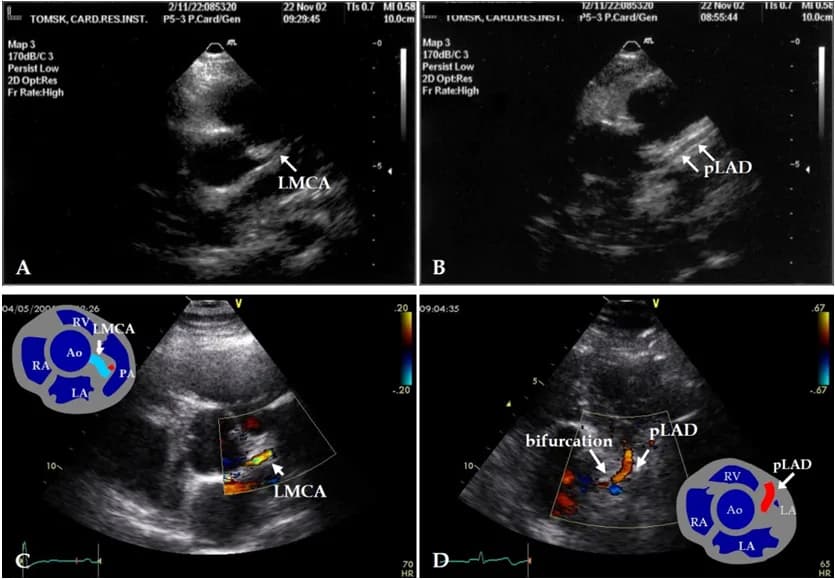

siêu âm timphẫu thuật timbệnh tim bẩm sinhthông liên thấtteo van động mạch phổi

Thông liên thất, teo van và động mạch phổi

Thông liên thất, teo van và động mạch phổi là bệnh tim bẩm sinh hiếm gặp, ảnh hưởng đến sự phát triển của tim và mạch má...